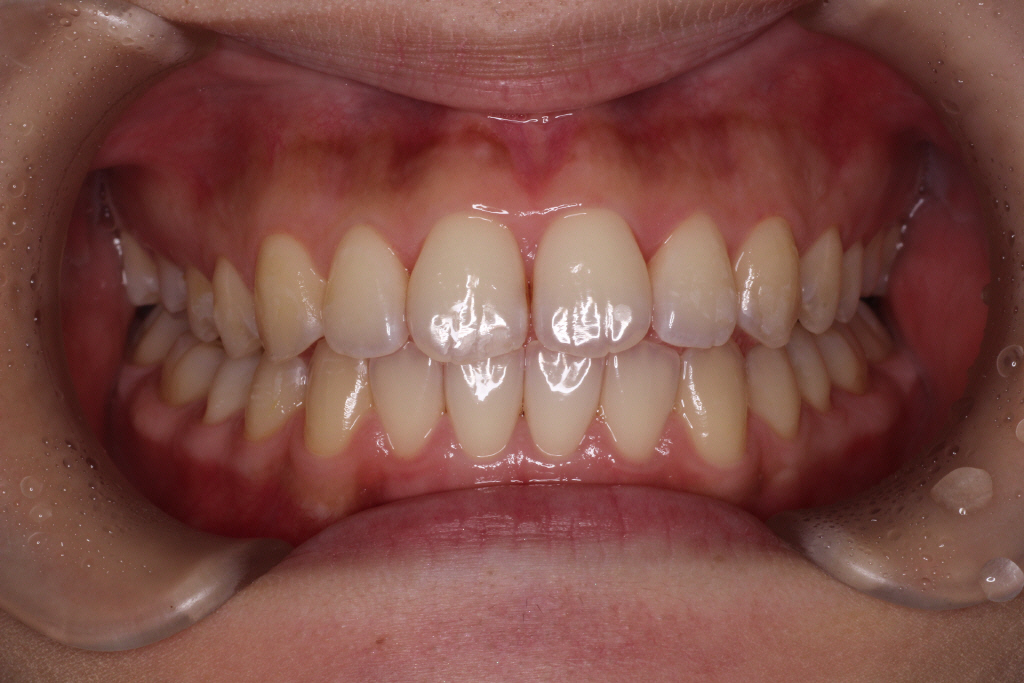

下が1回目のインビザラインが終わった時の写真です。気になっていた前歯のねじれはきれいに並びました。

もう少し噛み合わせを整えるために、アタッチメントを一度全部とりリファイメント(微調整)のお口の型どりをおこないます。